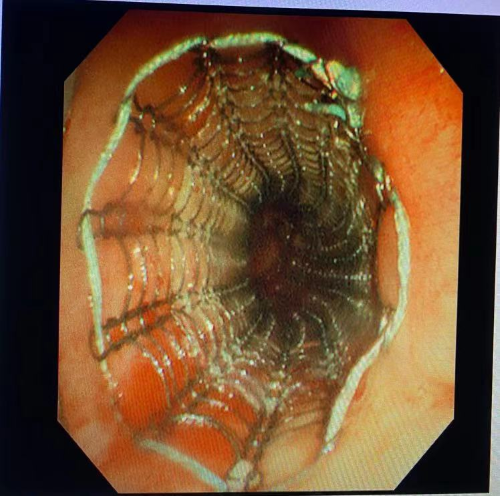

气道支架置入术前

左图主气管,右图左主支气管

置入硬镜后镜下可见右主开口完全被肿瘤组织堵塞,且肿瘤组织突入左主支气管开口堵塞管腔,左主开口狭窄。